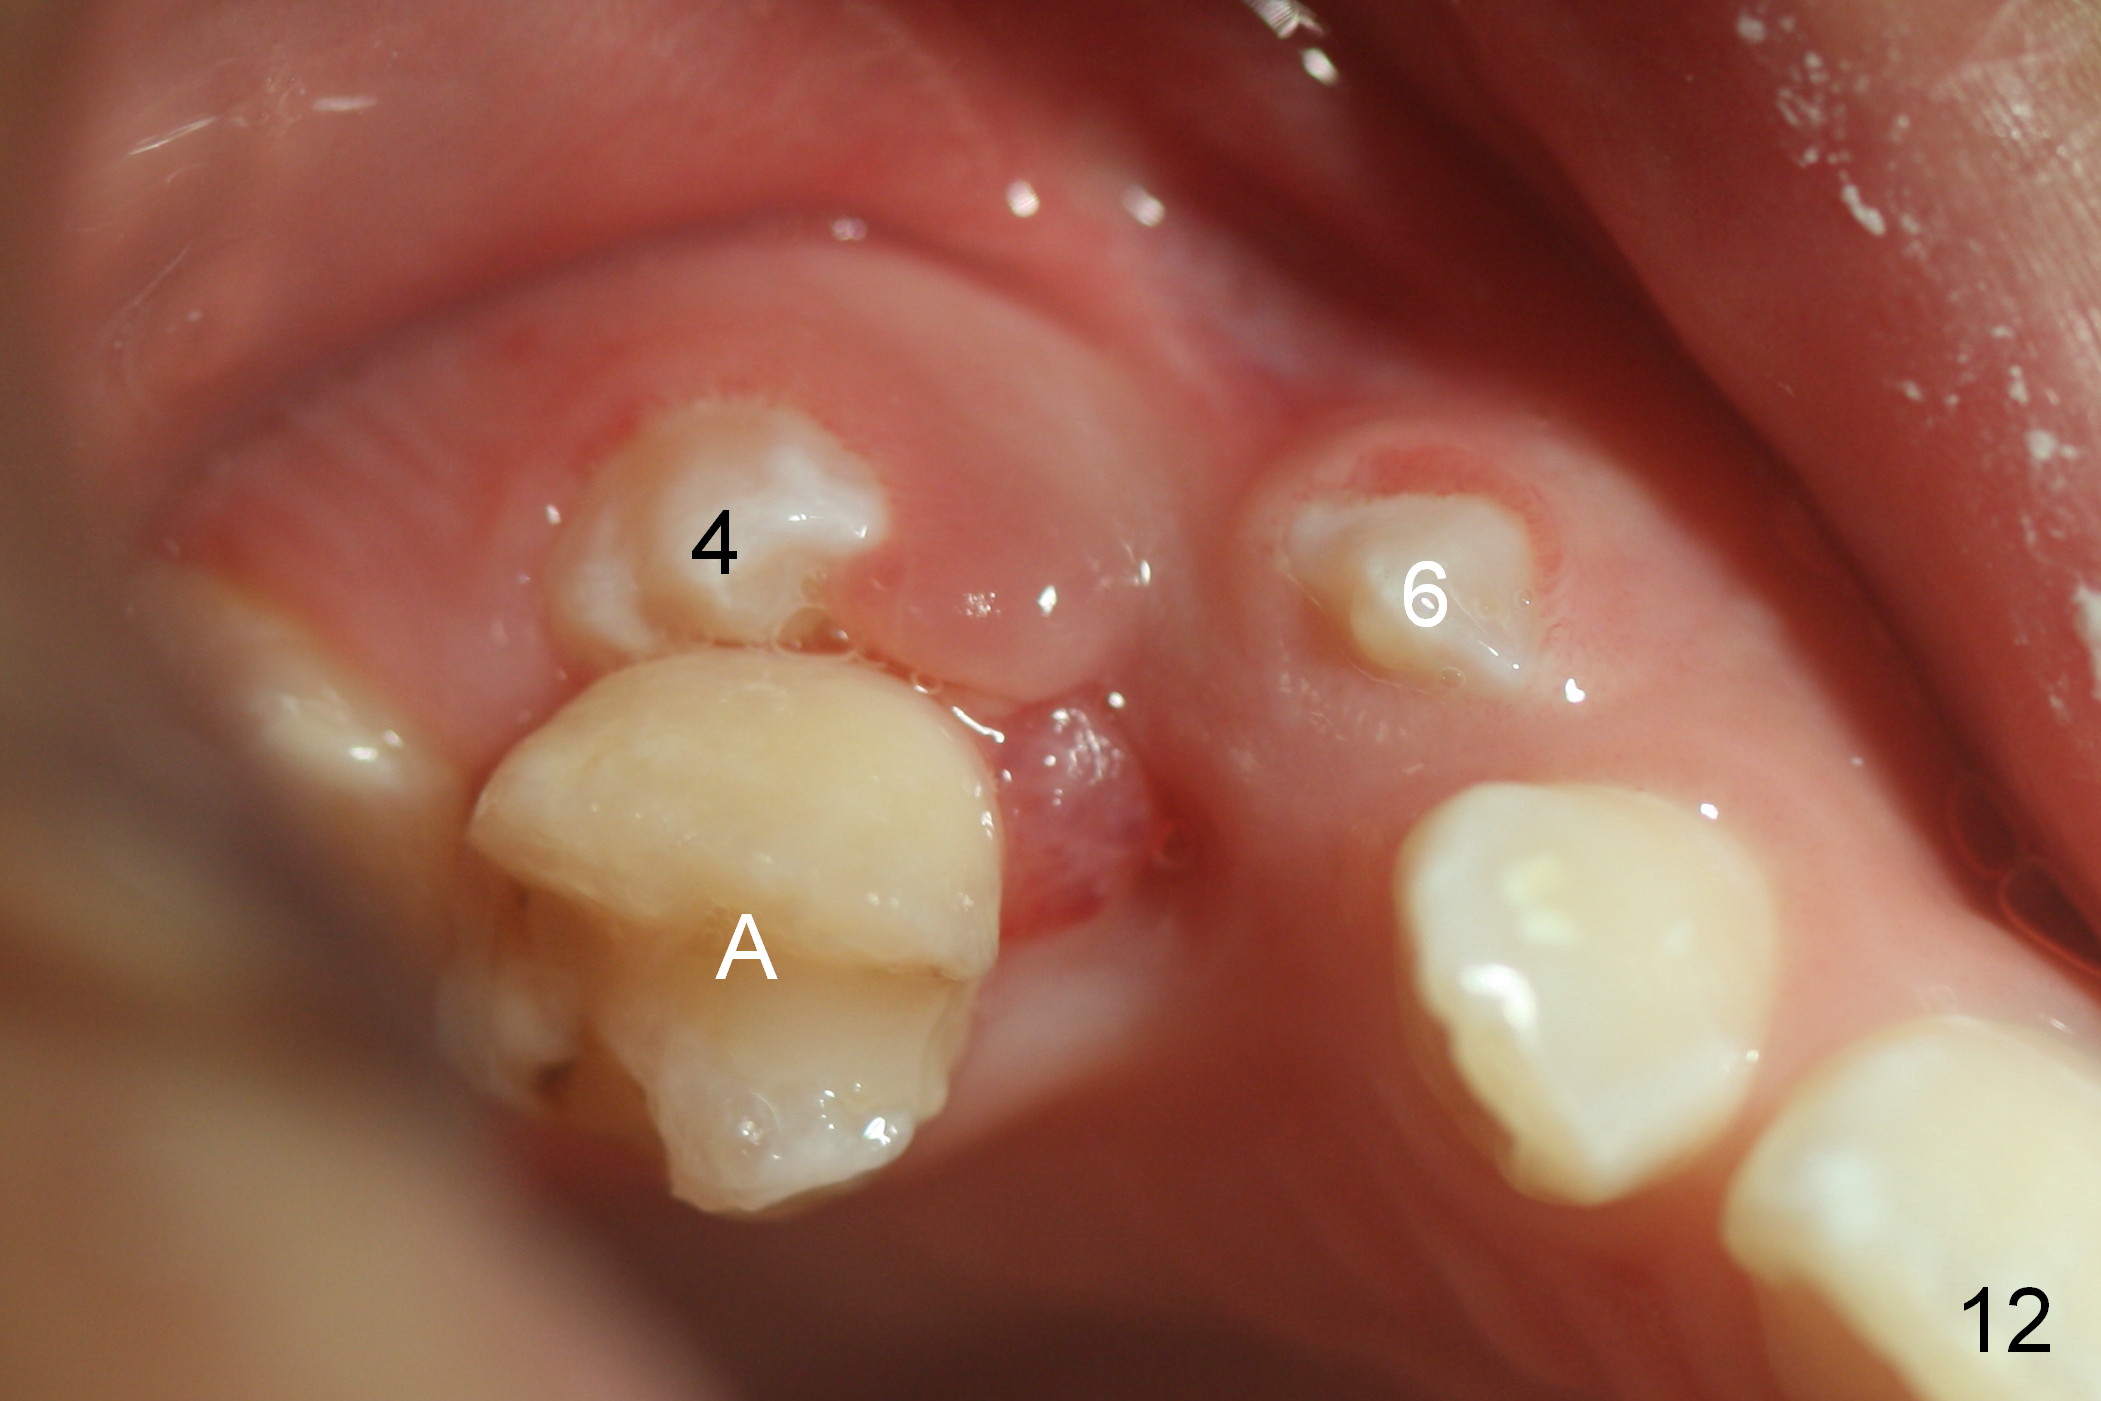

Another 1 month, the teeth #4 and 6 are erupting (Fig.11,12). The tooth A is to be extracted. It is assumed that the diastema between #7 and 8 (due to #7 mesial shift in turn due to #6 erupting, Fig.11 arrow (as compared to Fig.6 <)) will be closed once the tooth #6 erupts fully.